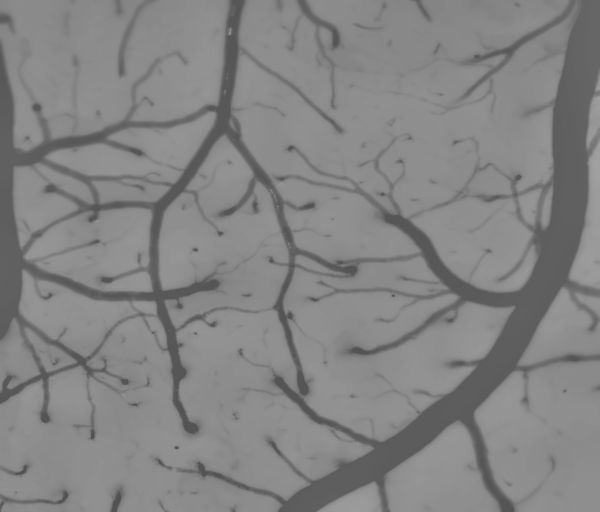

本文我们使用一张光照不均匀的血管图像来检验所实现算法的效果,如下图所示,可以看到原本图像的光照信息就是不均匀的,所以计算出来的背景图像上不同区域的明暗并不一样。

原图